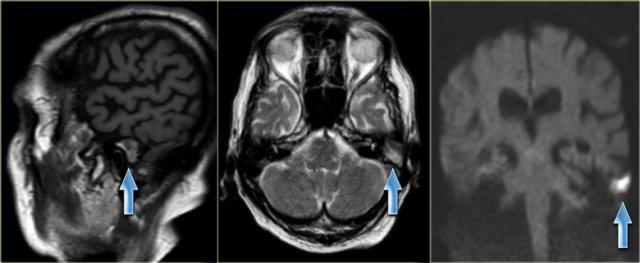

Nam giới 75 tuổi với cholesteatoma tái phát đã biết. Hình ảnh cho thấy khối có tín hiệu hỗn hợp trên chuỗi xung T1W mặt phẳng sagittal và tăng tín hiệu trên chuỗi xung T2W mặt phẳng axial. Khối tăng tín hiệu trên hình ảnh khuếch tán, cho thấy hạn chế khuếch tán. (các mũi tên)

Cholesteatoma có tín hiệu hỗn hợp trên chuỗi xung T1W và tăng tín hiệu trên chuỗi xung T2W.

MRI đặc biệt hữu ích trong việc đánh giá mức độ lan rộng của cholesteatoma vào hố sọ giữa và/hoặc hố sọ sau, cũng như phát hiện khả năng thoát vị của các cấu trúc nội sọ vào xương thái dương – đặc biệt sau phẫu thuật.

Sau khi tiêm thuốc tương phản từ tĩnh mạch, MRI có thể phân biệt mô hạt với tràn dịch.

MRI khuếch tán có thể phân biệt cholesteatoma – vốn có hạn chế khuếch tán – với các bất thường khác, đặc biệt là mô hạt – vốn có đặc điểm khuếch tán bình thường (hình minh họa).